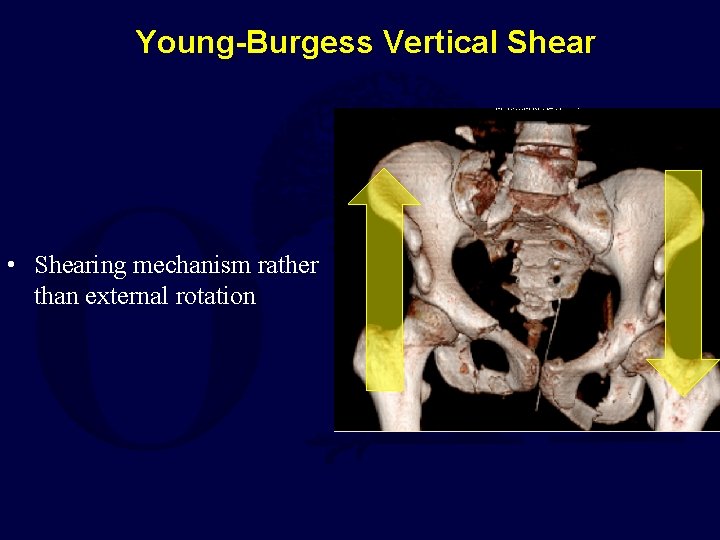

Young-Burgess Vertical Shear • Shearing mechanism rather than external rotation